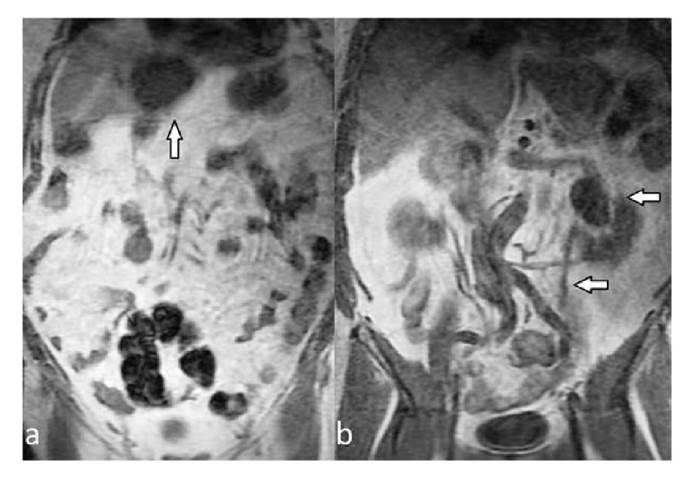

All extraspinal abnormalities detected in conventional sagittal T1 W and T2W images appeared in coronal-T1 W images. Most extraspinal MRI findings (27.6%) were related to the kidney or the ureters (42/152); of these, 22 were detectable in the sagittal/axial planes while 20 were detectable only in coronal-T1 W images. Of the pathologies related to the kidney and the ureters, 31 belonged to Category 1 and 11 to Category 2. After the kidney- related pathologies, the most common extraspinal MRI findings in the coronal- T1W sequence were those associated with the pelvic bones including the coxofemoral joints. Osteoarthritis/degenerative changes (n=16), nonspecific bone lesions (n=10), and bone metastases (n=9) were the most common extraspinal MRI findings while 23 were associated with the liver and 20 with the sacroiliac joints. Lesions that may be compatible with cyst or hemangioma in the liver (n=18) and sacroiliitis-related findings (n=15) related to sacroiliac joints were among the common findings (figures 1,2). Also, ovarian cysts/ masses (n=9), uterine fibroids (n=7), and surrenal masses (n=3) were some of the extraspinal MRI findings. Besides, less common MRI findings such as aortic aneurysm (n=2) and retroperitoneal fibrosis (n=1) were also recorded. The classification of extraspinal MRI findings is shown in tables 2 and 3. The grouping and number of patients in each group is also summarized in the cohort diagram (table 3 and figure 3).

Of the 152 extraspinal MRI findings detected in our study, 33 (22%) were detectable on conventional images, while 129 (78%) were visible only on coronal-T1W images, and 42 of the pathological extraspinal imaging findings were related to the kidneys and ureters. It is possible to detect many renal imaging findings in the axial plane, but the coronal plane allows for easier detection and characterization. The collector system enlargement from renal pathologies, complex cysts (Bosniak II and above), and cysts larger than 3 cm were accepted as associated with low back pain 15. After renal diseases, liver lesions, unilateral or bilateral sacroiliitis, coxofemoral disease, and iliac bone lesions were the most common pathological extraspinal MRI findings in our study. Findings compatible with metastasis from bone-derived pathologies, sacroiliitis, coxofemoral pathologies, and biliary dilatation were classified as possible pathologies associated with low back pain.